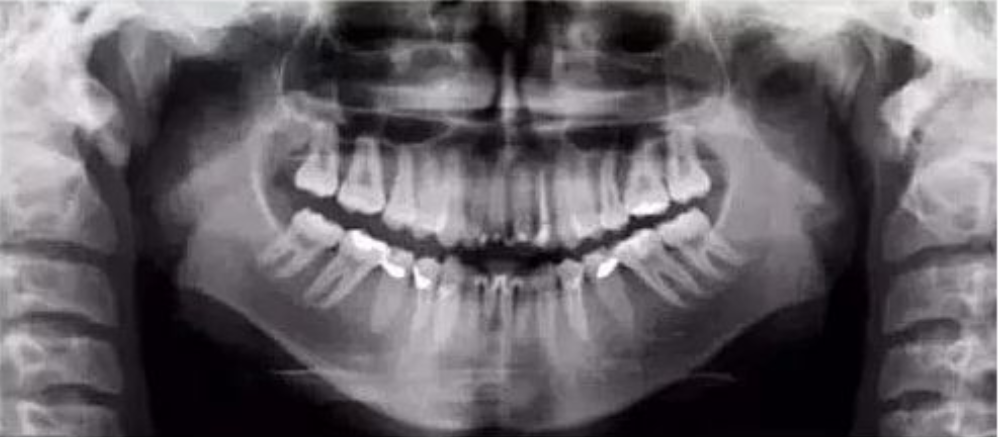

二、影像辐射穿透度不够,前牙显示较大

【失误原因】

定位聚焦激光束或自动对焦(Autofocus)激光束定位过靠前。

【解决方法】

将定位聚焦光束后移至侧切牙根尖位置。